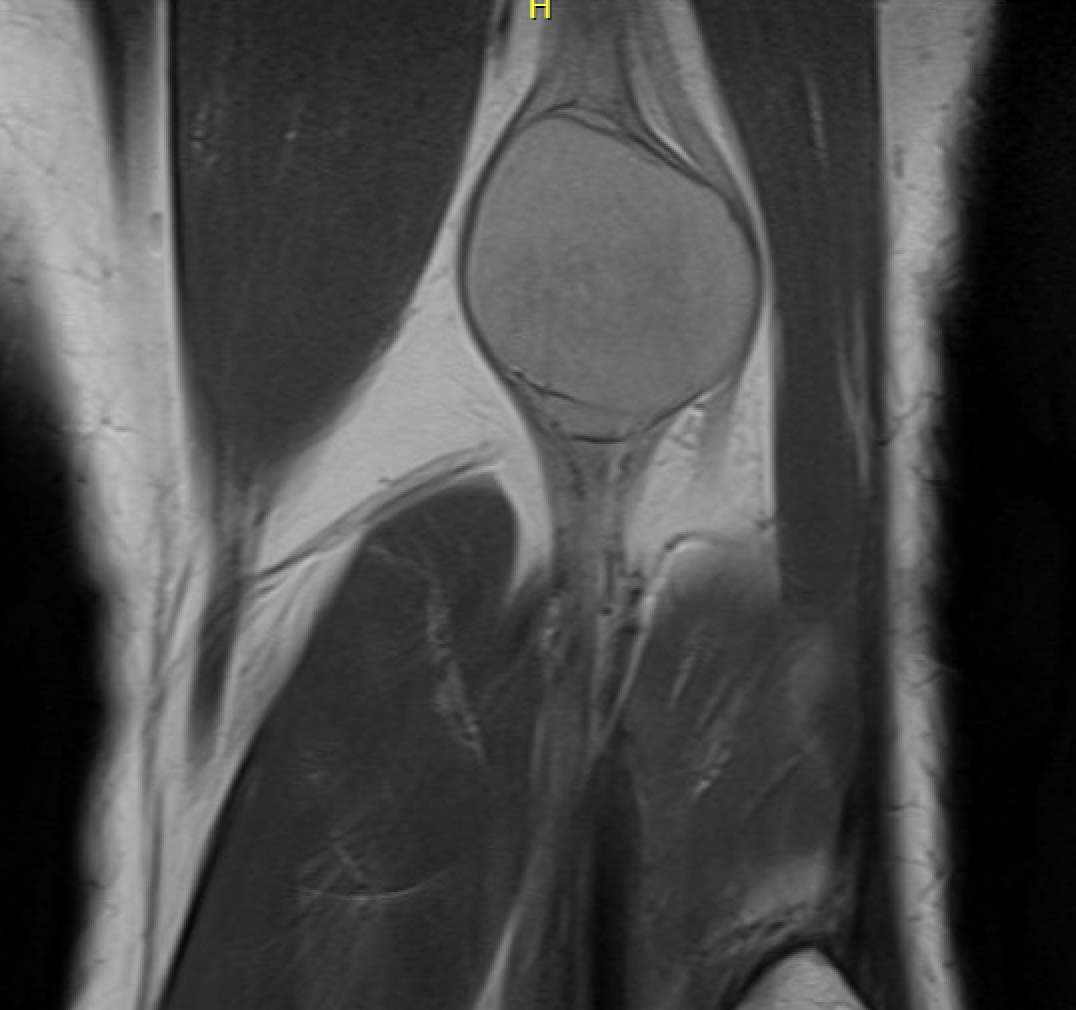

MRI

Target sign

- hypointense centrally

- hyperintense peripherally

Neurofibroma common peroneal nerve